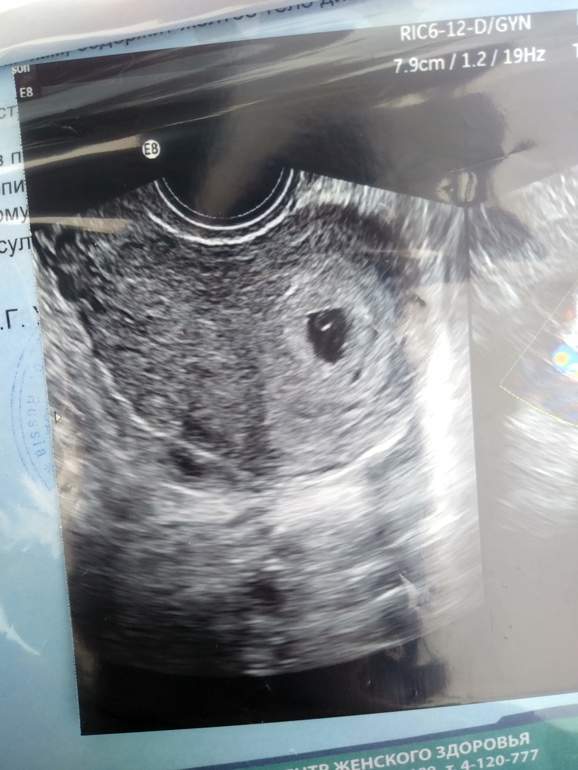

Это жм, у меня есть похожий снимок в дневнике , только жм маленький там совсем, а малыша ещё не видно вообще

Возможно эмбрион там где небольшая размытость наверху. А может быть она увидела эмбрион под другим ракурсом, но поймать не смогла. Вы не переживайте, у вас прекрасный жм, а на малыша ещё посмотрите😊 я вообще узи после такой бусинки как у вас вплоть до скрининга ни разу не делала, перед скинингом вся испереживалась, а вдруг я вообще это придумала😂а потом глянула в монитор узистке, а там человечек, ровненький, с ручками и ножками))) поверить не могла что мой

Больше похоже на мешочек, мне например под одним ракурсом эмбрион находили под другим мешочек. Эмбриончики обычно прячутся